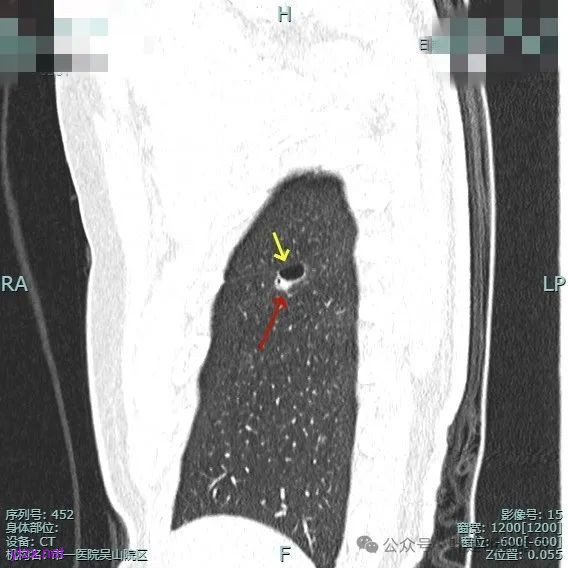

靶重建的影像上看,病灶的囊壁明显厚薄不均,有小血管进入,一侧的边似就是斜裂的样子。

囊壁有磨玻璃成分,边缘毛糙,有少许偏实性成分,仍有磨玻璃成分。

血管走向病灶,囊壁略不均。

此层见囊壁有较明显实性成分,血管进入明显。叶间裂侧平直。

混合密度,收缩力不明显,血管进入明显。

囊壁混合密度,整体轮廓清。

表面不平,血管进入,囊壁厚薄不均,紧贴叶间裂。

囊壁里面也有小空泡征。

混合密度但还是太致密,内壁毛糙不平。

病灶轮廓清楚,囊壁厚薄不均,贴着叶间裂与胸膜。